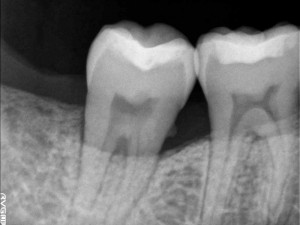

健康な骨

歯周病で溶けた骨

歯周病はサイレントキラーとも呼ばれ、本人が気付かないまま、歯ぐきの中の骨を溶かしていってしまいます。

末期になってはじめて痛みや腫れ、歯の揺れといった症状が起こることが多いので、非常に恐ろしい病気と言えます。

健康な骨であれば、歯を十分に支えることができるため、揺れて抜け落ちてしまうこともありません。しかし歯周病が進んでいくと、歯の周りの骨が溶けて歯を支えることができなくなってしまうため、歯が揺れてきて、ついには抜け落ちてしまいます。

歯ぐきの中に歯石が付着し、周りの骨が溶けています

さらに歯周病が進んでくると歯ぐきの中にも歯石や汚れがたまってきます。

歯石や汚れは「歯周病菌の基地」のようなものなので、歯ぐきの中に歯石があると歯周病菌による歯を支える骨が直接攻撃されてしまい、比較的早く骨が溶けていってしまいます。